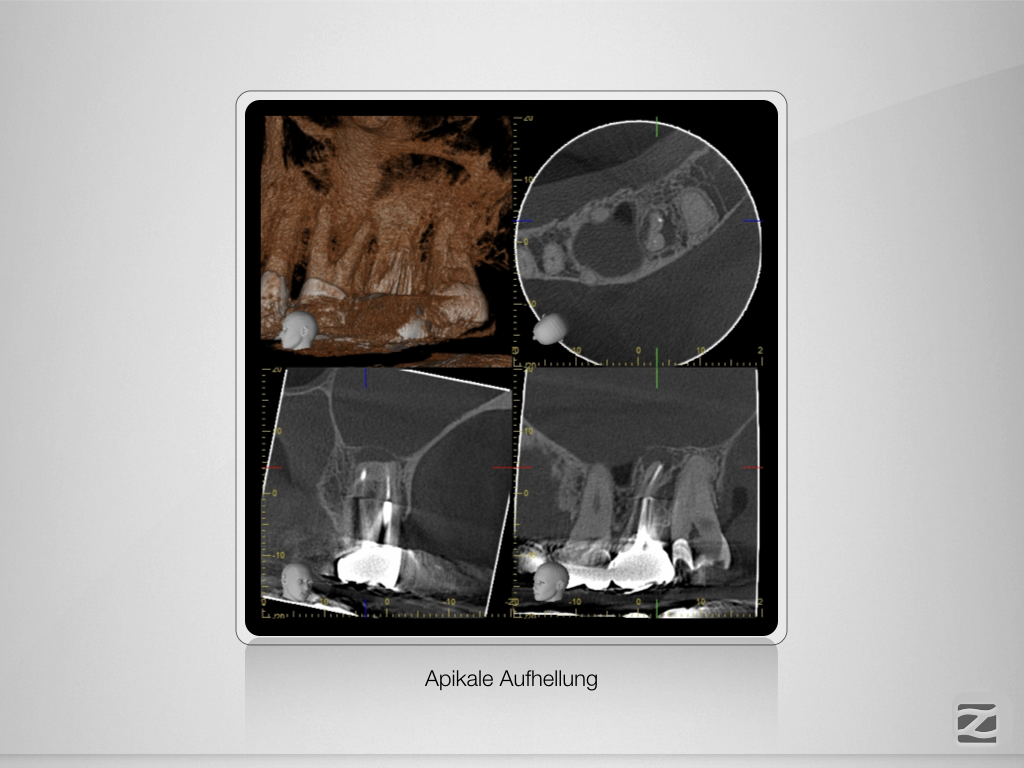

Der weiße Tod